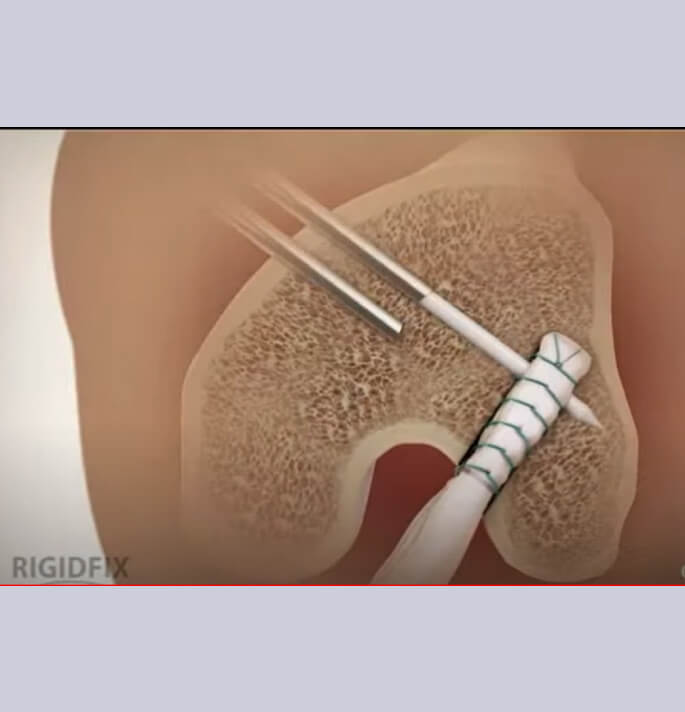

Bij een reconstructie (herstel) van de kruisband wordt een eigen peesgreffe (autologe) van de hamstrings (semitendinosus pees) of een strip van de quadricepspees gebruikt.

Deze peesgreffe wordt via een tunnel in het onderbeen (tibiale tunnel) in het gewricht gebracht (intra-articulair) en in een bovenbeen (femorale) tunnel gefixeerd.

Het fixatiemateriaal type RIGIDFIX welke in onze dienst wordt gebruikt heeft enkele belangrijke voordelen ten opzichte van andere systemen

Het materiaal is bio resorbeerbaar (wordt na verloop van tijd opgenomen door het lichaam zodat er geen vreemd materiaal ter plaatse blijft)

Doordat de fixatie extreem kort tegenaan het gewricht gebeurt ontstaat er geen verwijding van de tunnels en is het effect van uitrekking (stretching) van de greffe minder prominent wat vaker wordt gezien met corticale fixaties op afstand.